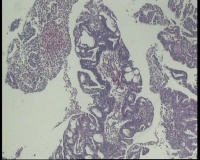

镜下见子宫内膜腺体异型增生,呈乳头状,筛网状排列,细胞核圆形,大小尚均匀,可见少量核分裂像,部分区域鳞化,间质少,部分区域无间质,间质有坏死